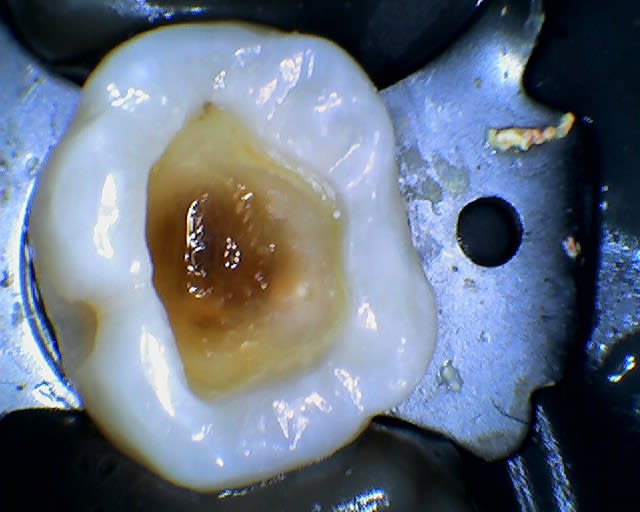

le curetage me paraissait ok et voila ce que j’obtiens...

Image radiotransparente est due peut être, bêtement, aux effets indésirables de ce type de matériau (contraintes + stress de polymérisation) .

- Est-ce une simple rétraction du matériau résineux?

Quel résultat lors du séchage de la cavité. Dentine séchée ou asséchée, dentine humide, dentine « mouillée » car : « un excès d’eau signifie la formation de lacunes au sein de l’interface ». Notons que les notions de séchage, d' humide, de légèrement mouillée est cliniquement difficile à apprécier car non quantifiable

Quelle méthodologie a été employée lors de l'insertion du composite : en un seul bloc ou stratification? D'où, quelle épaisseur du composite ?

Pourquoi une obturation OM au composite foulée sur une 16 sachant les risques de ce matériau ?

Pourquoi pas le choix d’obturation VI (fond de cavité) + composite ? Donc obturation type sandwich. L’adhérence du VI à la dentine n’est plus à démontrée.

Pourquoi pas, plus prosaïquement une obturation à l’amalgame d’Ag ?